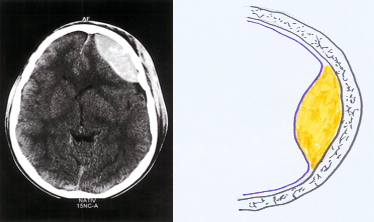

Epidural hematoma- CT head (axial section; noncontrast)

An epidural hematoma is visible as a solitary biconvex hyperdense lesion in the left frontotemporal region, causing a midline shift to the contralateral side.